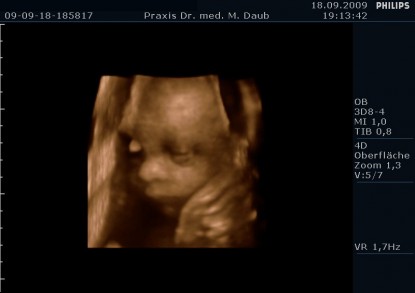

4D Ultraschall - 32. Schwangerschaftswoche